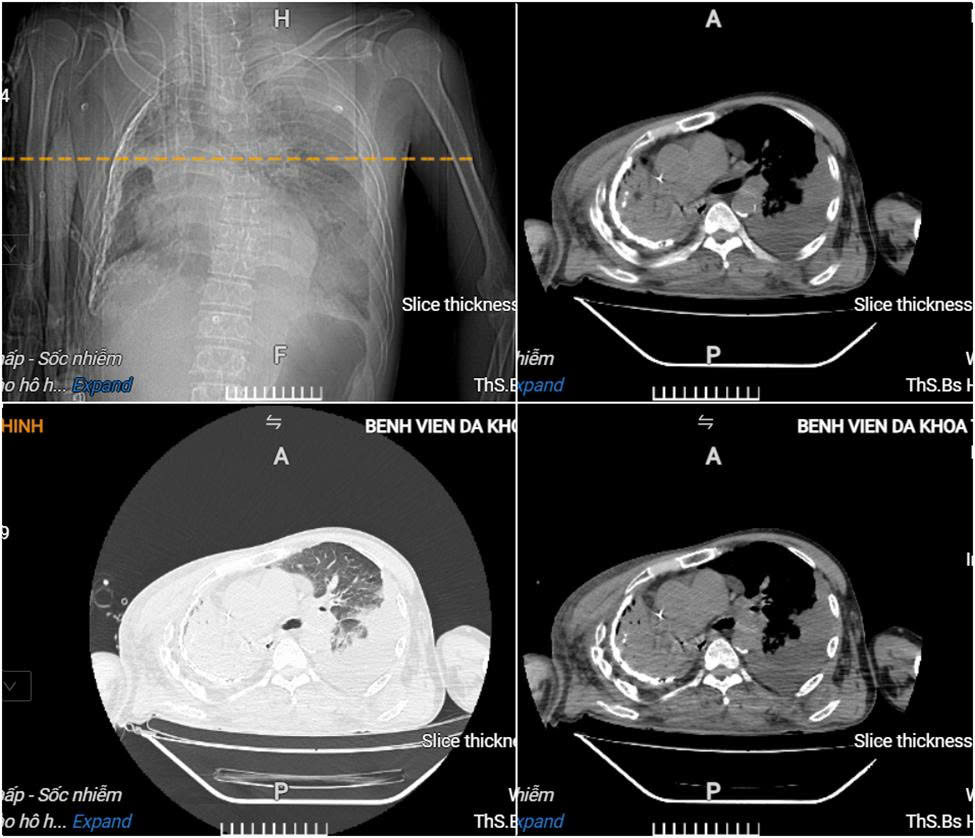

Người bệnh có tiền sử lao phổi, lạm dụng rượu, xuất hiện ho, sốt, khó thở nên được đưa vào Trung tâm Y tế Thanh Thủy điều trị. Do tình trạng diễn tiến nặng, người bệnh được chuyển đến Bệnh viện Đa khoa tỉnh Phú Thọ trong tình trạng kích thích, vật vã, khó thở nhiều, sốc nặng, huyết áp phụ thuộc thuốc vận mạch liều cao… Kết quả xét nghiệm ghi nhận toan chuyển hóa, suy đa tạng, nhiễm trùng – nhiễm độc nặng, rối loạn đông máu. Hình ảnh chụp CT ngực cho thấy có áp-xe phổi trái lớn, tràn dịch màng phổi phải.

Hình ảnh cắt lớp vi tính lồng ngực của người bệnh cho thấy có áp-xe phổi trái lớn, tràn dịch màng phổi phải